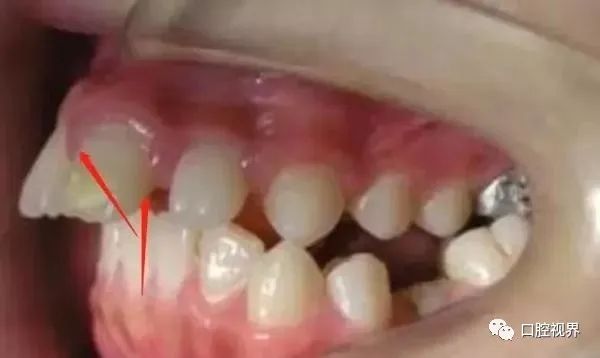

牙位异常(多生牙)

这些情况通常都是容易辨认,一经发现还是尽早前往正规的口腔医院处理一下。

此外,部分小朋友的乳牙没能按时下岗,从而导致牙缝变大,严重甚至还会使得恒牙不能正常萌出。